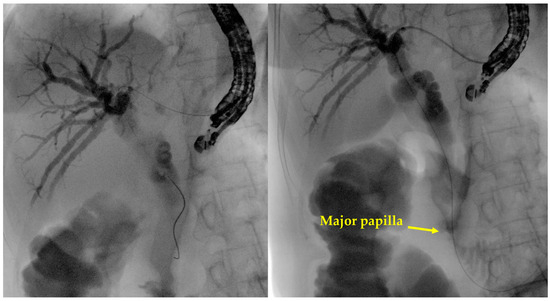

- Tract dilation

- Stent positioning